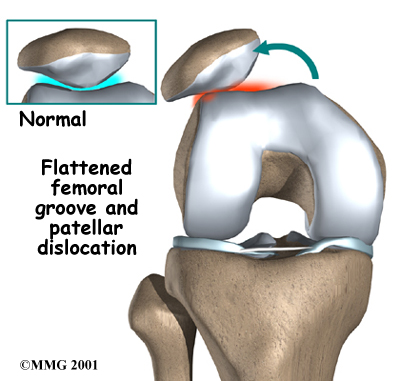

Finally, anatomic variations in the bones of the knee can occur such that one side of the femoral groove is smaller than normal. This creates a situation where the groove is too shallow, usually on the outside part of the knee. People who have a shallow groove sometimes have their patella slip sideways out of the groove, causing a patellar disclocation. This is not only painful when it occurs, but it can damage the articular cartilage underneath the patella. If this occurs repeatedly, degeneration of the patellofemoral joint occurs fairly rapidly.

Finally, anatomic variations in the bones of the knee can occur such that one side of the femoral groove is smaller than normal. This creates a situation where the groove is too shallow, usually on the outside part of the knee. People who have a shallow groove sometimes have their patella slip sideways out of the groove, causing a patellar disclocation. This is not only painful when it occurs, but it can damage the articular cartilage underneath the patella. If this occurs repeatedly, degeneration of the patellofemoral joint occurs fairly rapidly.

People who have a high-riding patella are also at risk of having their patella dislocate. In this condition, called patella alta, the patella sits high on the femur where the groove is very shallow. Here the sides of the femoral groove provide only a small barrier to keep the high-riding patella in place. A strong contraction of the quadriceps muscle can easily pull the patella over the edge and out of the groove, leading to a patellar dislocation. Patella alta is most common in girls, especially those who have generalized laxity (looseness) in their joints.